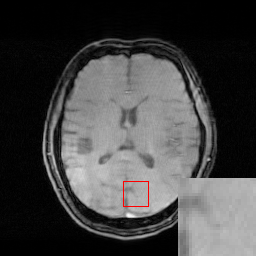

We illustrate with reconstructions for three CS-MRI methods: TLMRI (transform learning MRI) [25], PANO (patch-based nonlocal operator) [23] and GBRWT (graph-based redundant wavelet transform) [14]. The PANO and GBRWT models achieve impressive reconstruction qualities because they use an nonlocal prior and adaptive graph-based wavelet transform to exploit image structures. In TLMRI, the sparsifying transform learning and the reconstruction are performed simultaneously in more efficient way than DLMRI [24]. The three methods represent the state-of-the-art performance in the non-deep CS-MRI models. In Figure 2, we show the reconstructions error for zero-filled (itself a potential reconstruction “algorithm”), TLMRI, PANO and GBRWT on a complexed-valued brain MRI using 30%percent3030\% Cartesian under-sampling. The error display ranges from 0 to 0.2 with normalized data. The parameter setting will be elaborated in the Experiment Section V.

We also consider the deep learning DC-CNN model [26] as the guide module. We also give the reconstruction error in Figure 2. We observe the zero-filled, TLMRI, PANO, GBRWT and DC-CNN models all suffer the structural reconstruction errors, while the DC-CNN model achieves the highest reconstruction quality with minimal errors because of its powerful model capacity. Another advantage of this CNN model is that, once the network is trained, testing is very fast compared with conventional sparse-regularization CS-MRI models. This is because no iterative algorithm needs to be run for optimization during testing since the operations are a simple feed forward function of the input. We compare the reconstruction time of TLMRI, PANO, GBRWT and DC-CNN for testing for Figure 2 in Table I.

Figure 2: The reconstruction error of a brain MRI using zero-filled, TLMRI, PANO, GBRWT and DC-CNN under 1D 30%percent3030\% under-sampling mask.